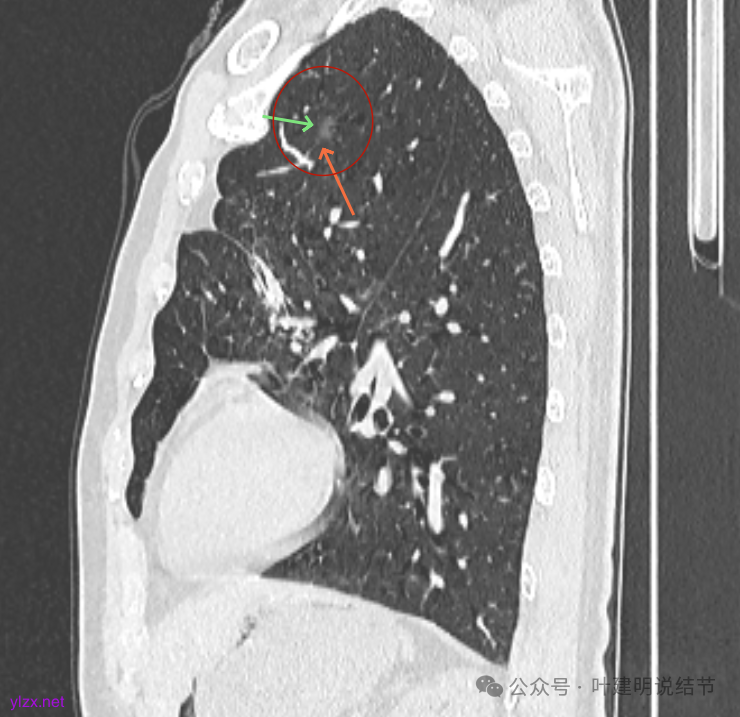

矢状位见右上病灶也是纯磨,灶内的血管可见,表面部分有细毛刺,整体轮廓与边界清楚。